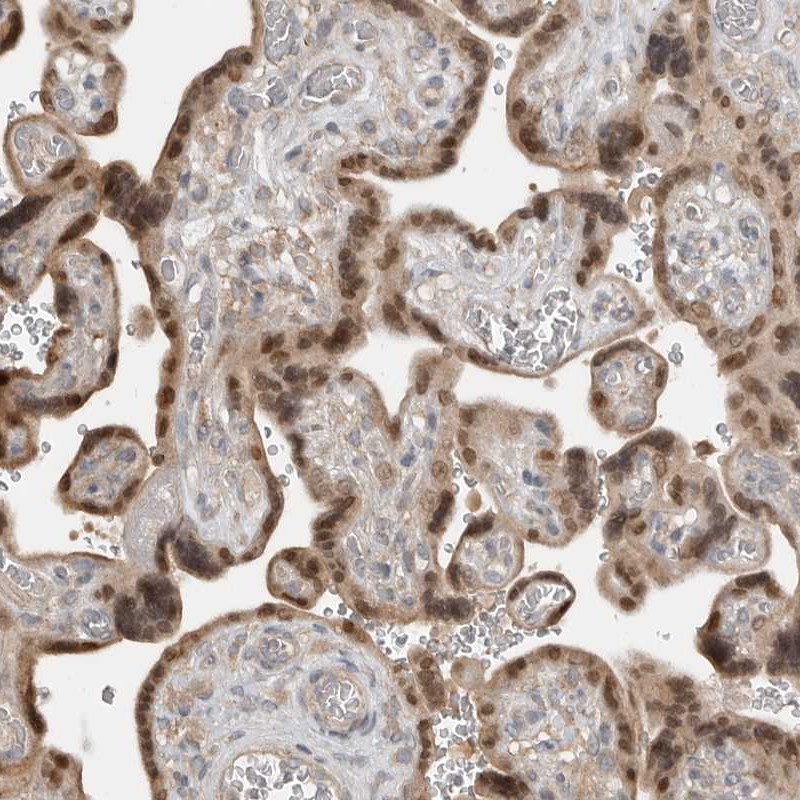

Immunohistochemical staining of human placenta shows nuclear positivity in trophoblastic cells.